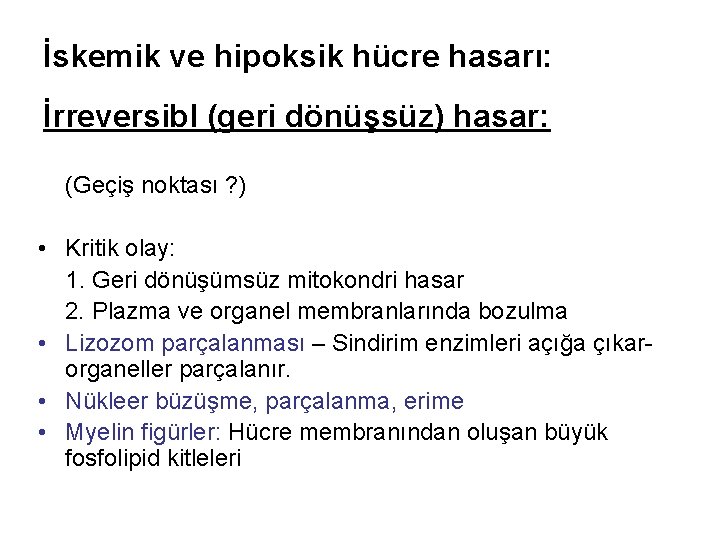

İskemik ve hipoksik hücre hasarı: İrreversibl (geri dönüşsüz) hasar: (Geçiş noktası ? ) • Kritik olay: 1. Geri dönüşümsüz mitokondri hasar 2. Plazma ve organel membranlarında bozulma • Lizozom parçalanması – Sindirim enzimleri açığa çıkarorganeller parçalanır. • Nükleer büzüşme, parçalanma, erime • Myelin figürler: Hücre membranından oluşan büyük fosfolipid kitleleri